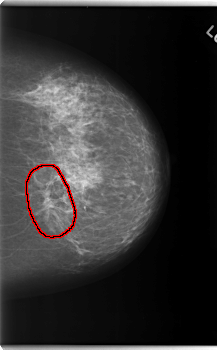

C_0173_1.LEFT_MLO

LEFT_MLO LINES 5880 PIXELS_PER_LINE 3552 BITS_PER_PIXEL 12 RESOLUTION 50 OVERLAY

FILE: C_0173_1.LEFT_MLO.OVERLAY

TOTAL_ABNORMALITIES 1

ABNORMALITY 1

LESION_TYPE MASS SHAPE IRREGULAR MARGINS ILL_DEFINED

ASSESSMENT 5

SUBTLETY 5

PATHOLOGY MALIGNANT

TOTAL_OUTLINES 1

BOUNDARY